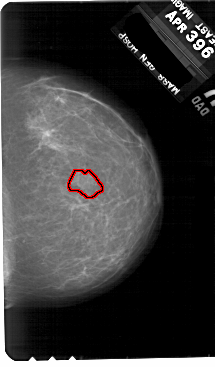

FILE: A_1886_1.RIGHT_MLO.OVERLAY

TOTAL_ABNORMALITIES 1

ABNORMALITY 1

LESION_TYPE MASS SHAPE IRREGULAR MARGINS ILL_DEFINED

ASSESSMENT 4

SUBTLETY 3

PATHOLOGY BENIGN

TOTAL_OUTLINES 1

BOUNDARY

RIGHT_MLO LINES 5491 PIXELS_PER_LINE 3451 BITS_PER_PIXEL 12 RESOLUTION 43.5 OVERLAY